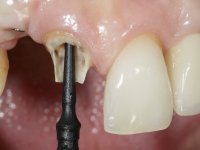

Segunda Fase.

Após 5 anos da primeira intervenção, a paciente surge na consulta com uma peri-implantite nos implantes colocados no local dos dentes 1.2 e 4.6. Começamos por abordar a peri-implantite no local do dente 2.2. Foi feita uma ponte provisória de laboratório em acrílico com 2 elementos. O dente 1.1 como pilar e o 1.2 como pôntico, este último apresentava um apoio distal. A coroa do 1.2 foi removida do coto com um corte longitudinal feito com turbina e depois foi fraturada com um mini luxador. O coto foi de seguida desaparafusado do implante. Fez-se o mesmo procedimento para remover a coroa do 1.1. O dente 1.1 foi re-preparado e a ponte provisória foi rebaseada em boca com acrílico autopolimerizável. Feito o correto acabamento e polimento da provisória foi feita a sua cimentação temporária com cimento de policarboxylato. Numa consulta posterior. foi feita a remoção da ponte provisória, feita a cirurgia para explantação do implante, colocou-se um novo implante e fez-se a regeneração óssea da zona com uma membrana não reabsorvível. 3 meses após foi removida a coroa do implante colocado no 4.6. Foi feito um corte horizontal com turbina na zona cervical e com um mini luxador descolou-se a coroa do coto. Após este procedimento fez-se a explantação do implante. Após 6 meses foi colocado um novo implante no local do 4.6. Após a osteointegração foi feita a impressão com a técnica de moldeira aberta e foi confecionada em laboratório uma coroa aparafusada sobre o implante. Aprovada pela paciente foi apertada definitivamente em boca. Após 1 mês removemos a ponte provisória antero-superior, reforçamos o dente 1.1 com um poste intra- radicular e reconstruimos o coto com uma resina de polimerização dual. Nessa mesma consulta expomos o implante colocado no 1.2 e fizemos uma impressão pela técnica de moldeira aberta com silicone de dupla viscosidade e presa rápida. No laboratório foi feita uma ponte provisória de 2 elementos, aparafusada sobre o implante e cimentada sobre o dente. A primeira ponte provisória foi removida e colocada a segunda aparafusada sobre o implante. A linha de acabamento cervical do 1.1 foi rebaseada com resina composta durante o aperto do parafuso do implante. Depois foi removida, foram feitos os acabamentos e finalmente apertada sobre o implante e cimentada temporariamente sobre o dente. Após 2 meses de maturação dos tecidos moles em função do perfil de emergência criado pela nova ponte provisória, pudemos avaliar a estética conseguida em conjunto com a paciente. Neste longo processo o dente 2.1 teve que fazer um tratamento endodôntico. Decidiu-se assim fazer também uma coroa no dente 2.1.O dente 2.1 foi preparado na mesma consulta em que se fez a impressão ao implante. A ponte provisória foi utilizada para individualizar a peça de transferência, copiando o seu perfil de emergência e em seguida foi realizado o afastamento gengival com caolino. A impressão foi feita com a técnica de moldeira aberta com silicone de dupla viscosidade e presa rápida. Após a escolha da cor, a impressão foi enviada  para o laboratório onde foram confecionadas 2 coroas  com infraestrutura em Zr. revestidas a cerâmica para os dentes 1.1 e 2.1 e uma coroa aparafusada sobre o implante no dente 1.2. O trabalho final foi aprovado pela paciente e foi colocado definitivamente em boca. A coroa sobre o implante foi aparafusada com 35 N e as coroas foram cimentadas com cimento de ionómero de vidro reforçado com resina.